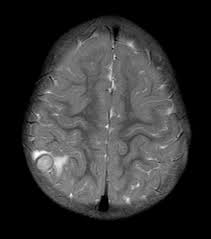

ενδοκρανιακό φυμάτωμα

φυματιώδης εγκεφαλοπάθεια